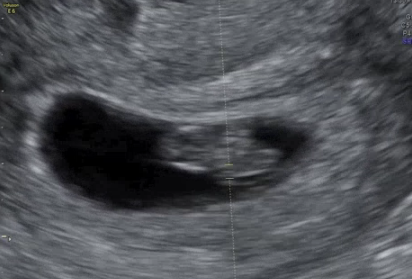

10주차는 배초음파를 시도해볼 수 있는 전환점입니다.

병원마다 다르지만, 일부 병원에서는

질초음파 대신 복부 위에서 보는 배초음파로 전환하기도 해요.

태아 크기: 약 3~4cm 정도

머리와 몸통: 비율은 여전히 머리가 크지만, 사람 형태에 가까워짐

팔다리 움직임: 드문드문 관찰 가능

심장박동: 분당 120~160회로 규칙적

복부 초음파로 태아의 실루엣을 보는 그 순간,

손가락, 발가락의 작은 움직임이 포착되면

그 작디작은 생명이 얼마나 생동감 있게 살아 있는지를

가슴 깊이 느끼게 됩니다.